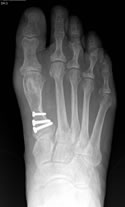

On June 2nd the surgery took place and everything went like clockwork. I left the hospital on crutches and elevated my foot at home. My pain was "minimal", just as the doctor said. The next day I received a call from Dr. Leavitt to see how I was doing (this never happens!) and I also got a call from the nurses at the surgical unit to see if I had any questions or problems. After two weeks I returned for my first checkup. The stitches came out and the pin was removed. A new cast was put on and off I went again. I had several appointments following surgery, and each time I was reassured by Dr. Leavitt with his smile, wit and easy conversational style. I came with my list of questions and he answered every one. Each time I went in nervous and I left with a big smile.

My new foot looks great. My physical therapist said she thought it looked beautiful and that was not always the case. I can barely see where the incision was. The eight weeks that I was non-weight bearing was a small price to pay in the scheme of life to have a good foot under me afterward. I was forewarned to follow instructions and "Take Care of My Work" and it paid off. I'm glad I had the surgery and I would do it all again. If you are in need of a foot doctor, look no further; call Dr. Ken Leavitt.